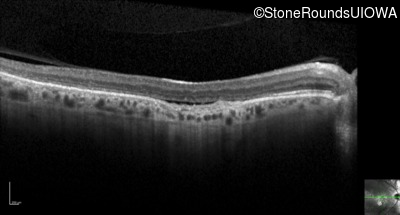

Optical Coherence Tomography - Right - 20/100 +2

Exemplar / OCT Stack

OCT Stack

Optical Coherence Tomography - Left - 20/125